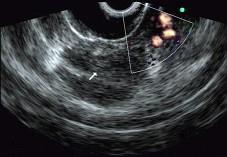

问题 男性,50岁,上腹隐痛,食欲不振3个月。1个月来出现黄疸且进行性加深,体重明显减轻,查体全身明显黄染,肝未触及,深吸气时可触到肿大胆囊底部,无触痛。化验血胆红素15mg/dl,尿检胆红素阳性图中胰腺病变可能的诊断是 ( )

选项 A.正常 B.胰腺囊肿 C.慢性胰腺炎 D.胰腺囊腺癌 E.胰腺癌

答案 E